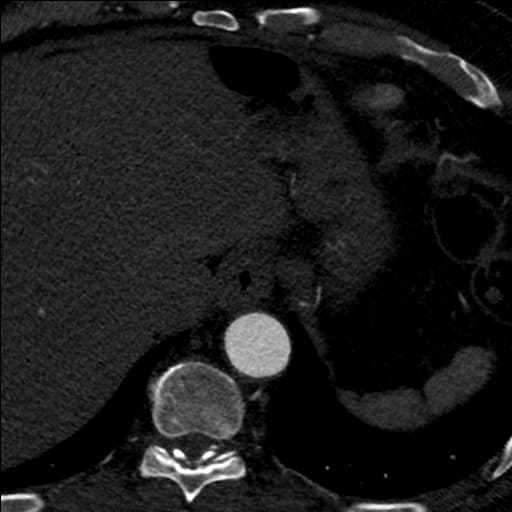

Thiết bị đóng ống động mạch còn thông (patent ductus arteriosus closure device) được đặt thành công tại vị trí ống động mạch, nằm giữa động mạch chủ (aorta) và động mạch phổi (pulmonary artery). Thiết bị hiện diện đúng vị trí, không di lệch, không thấy bằng chứng của rò rỉ qua thiết bị (device leak) hoặc thuyên tắc huyết khối (thromboembolism). Không thấy di chứng vị trí đặt thiết bị (device-related complications) như tổn thương động mạch phổi hoặc động mạch chủ.

Ghi chú (Note): Thiết bị đóng ống động mạch còn thông là dụng cụ can thiệp được sử dụng để đóng kín ống động mạch còn thông – một dị tật tim bẩm sinh ở trẻ sơ sinh hoặc người lớn. Việc đánh giá hình ảnh sau can thiệp nhằm xác nhận vị trí đúng, hiệu quả đóng kín và phát hiện sớm các biến chứng có thể xảy ra.